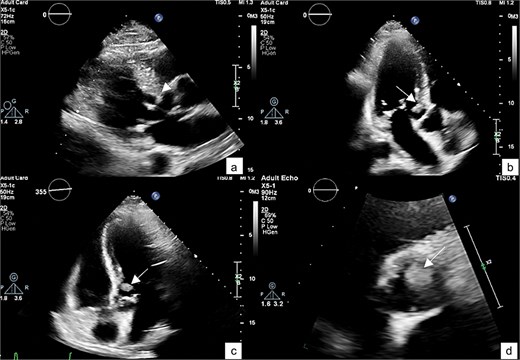

The patient underwent surgical excision of the LVOT mass via a median sternotomy. Cardiopulmonary bypass (CBP) was established using arterial cannulation in the ascending aorta and single, two-stage venous cannulation via the right atrium. An oblique aortotomy was performed to access the LVOT, and the mass was completely excised. The aorta was closed with 4–0 Prolene, and the excision site was inspected to ensure no residual tissue. Hemostasis was achieved, and CBP was weaned off once adequate cardiac function was confirmed. Two tube drainages in pericardial and mediastinal spaces. The pericardium was closed, with a total CBP time of 45 min, an aortic cross-clamp time of 27 min, and a total operative time of 3 h and 12 min. Gross pathology showed a 1 × 1 × 0.3 cm irregular, soft, grey-white polypoid mass. Histology examination of the mass revealed multiple branching papillary fronds with a central avascular collagen, lined by a layer of hyperplastic epithelial cells, consistent with papillary fibroelastoma (Figs 3 and 4).

Intraoperative view showing mass attached to the left ventricular outflow tract (a). A gross specimen of the excised mass (b).